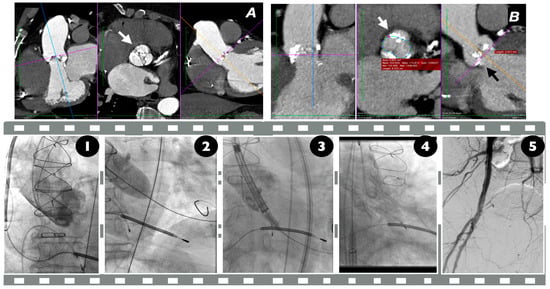

10. Implantation

- Gutierrez, L.; Boiago, M.; De Biase, C.; Oliva, O.; Laforgia, P.; Feliachi, S.; Beneduce, A.; Dumonteil, N.; Tchetche, D. Transcatheter Aortic Valve Implantation for Bicuspid Aortic Valve Disease: Procedural Planning and Clinical Outcomes. J. Clin. Med. 2023, 12, 7074. [Google Scholar] [CrossRef]

- Xiong, T.Y.; Ali, W.B.; Feng, Y.; Hayashida, K.; Jilaihawi, H.; Latib, A.; Lee, M.K.; Leon, M.B.; Makkar, R.R.; Modine, T.; et al. Transcatheter aortic valve implantation in patients with bicuspid valve morphology: A roadmap towards standardization. Nat. Rev. Cardiol. 2023, 20, 52–67. [Google Scholar] [CrossRef] [PubMed]